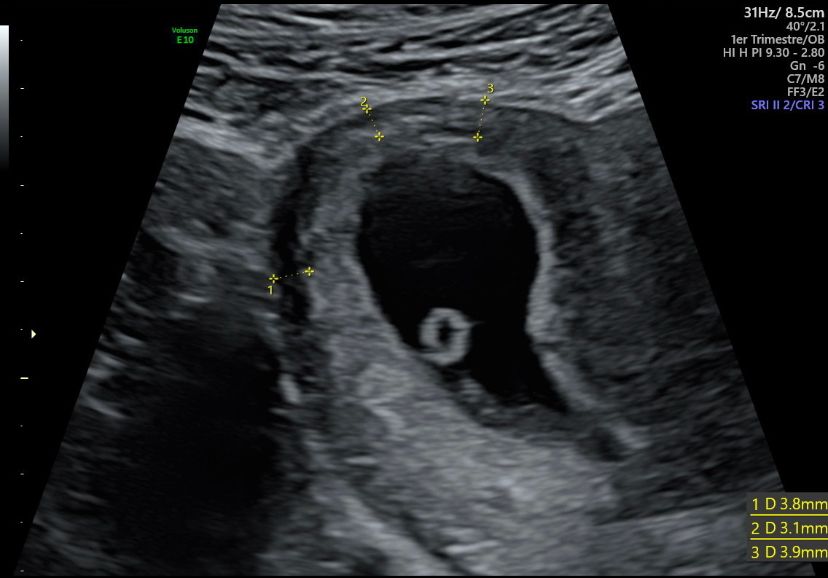

И вот 6 недель ровно я приезжаю эмбрион на месте сб + , но мне говорят что место мой мальчик выбрал неудачное… что возможно это вб, эмбрион прикрепился в на выходе из трубы, в этом месте где вроде бы уже матка, но ткани трубные и при росте пя матка может просто порваться и в итоге кровоизлияние с очень большим процентом летальных исходов. Врач сказала что меня отправляют на экспертное узи , если врач подтверждает , то делают чистку, так как моя жизнь в приоритете. Вы не представляете сколько слез было пролито …

Через два дня новое узи, гробовая тишина и вердикт «я склонен предполагать все же, что у вас маточная беременность, но надо следить» самое тонкое место миометрия у меня составляло 3,5мм, а дальше начались еженедельные узи , на которые я шла с замерением сердца, миометрий так и оставлялся 3.5 пя расположилось в правом рогу и занимало там все место ) я наблюдала как моя коеветочка растёт, но были очень страшно и за себя и за Малыша, не буду скрывать, но плакала я часто. за это время я прочитала все публикации зарубежных врачей на тему угловой беременности и понимала , что тут баш на баш, сомнения были только из-за меометрия , который по исследованиям должен был быть минимум 5мм. Так мы дожили до первого скрининга, на котором нам сказали что 95% прогноз что все будет хорошо, и первое предположение что у нас будет сын ))